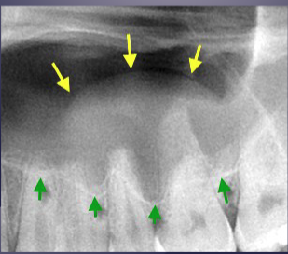

what’s the arrow pointing to

periosteal bone formation aka periostitis aka “onion skin” + mucosal thickening aka mucositis

2 radiographic signs of pericoronitis

periosteal reaction

sclerotic bone reaction (radiopaque)

what are the white + black arrows

white: periosteal rxn

black: sclerotic bone rxn

of pericoronitis